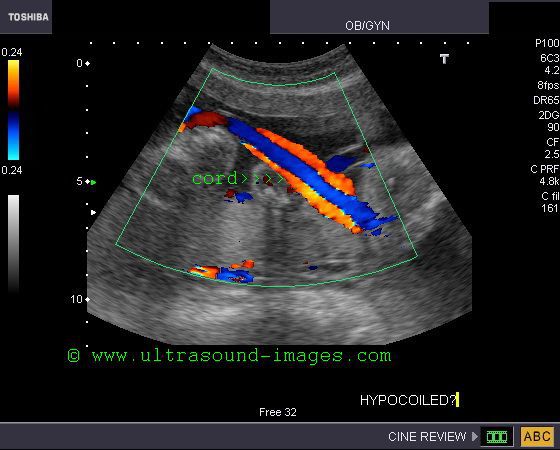

Hypocoiled umbilical cord

The normal umbilical cord extends from the placenta to the fetal umbilicus, twisting (coiling) as it traverses the distance between these two points. The umbilical cord contains two umbilical arteries and an umbilical vein which are normally coiled. Uncoiling or hypocoiled umbilical arteries are associated with increased fetal morbidity, including small for gestational age babies (fetuses). The above ultrasound and color Doppler images show an almost straight umbilical cord with almost no coils (hypocoiled cord). Such ultrasound findings are also associated with increased incidence            (almost 64 %) of abnormal umbilical cord insertions, ie: marginal or velamentous. This case and images are courtesy of    Dr. Durr -e-Sabih, Pakistan.